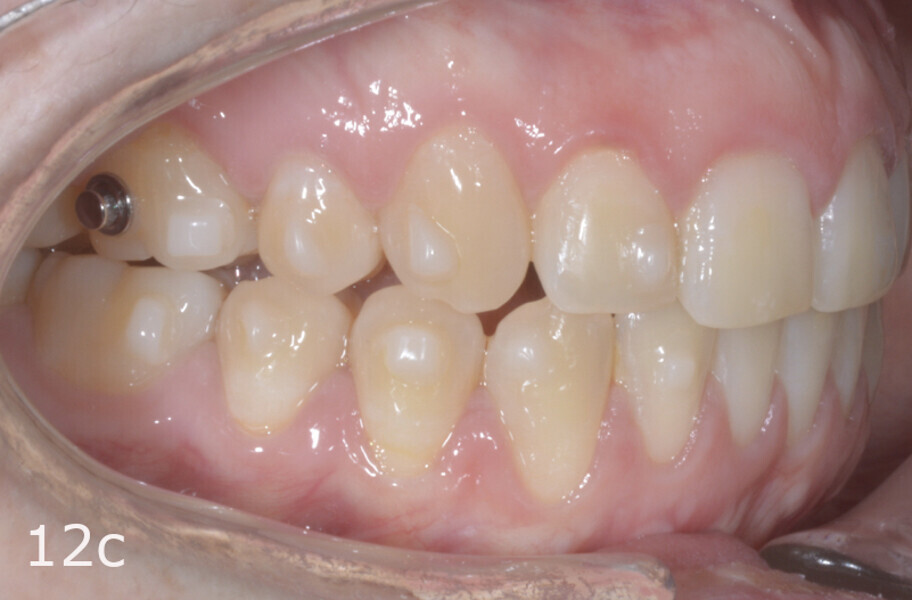

The treatment objectives included closing the anterior open bite, achieving a bilateral Angle Class I relationship and a proper overjet and overbite, correcting the midline discrepancies, and achieving a profile harmonisation. The treatment plan consisted of orthodontic camouflage treatment with asymmetric distalisation in three of the four quadrants using Invisalign aligners (Align Technology) and third molar extraction. The Invisalign Comprehensive package was chosen, and 63 pairs of aligners were used (Figs. 7–10). Each aligner was worn for 20 hours a day for one week each. The use of Class III elastics on both sides was indicated. Afterwards, ten refinement aligners were needed to improve the interdigitation on the right side (Figs. 11 & 12).

The total treatment time was 15 months. An Angle Class I relationship was established along with adequate anterior and canine guidance, establishing a functional occlusion. This not only ensures optimal masticatory function but also protects the teeth and the temporomandibular joint from excessive force. Maxillary and mandibular fixed retention were installed at the end of the treatment (Figs. 13–19).